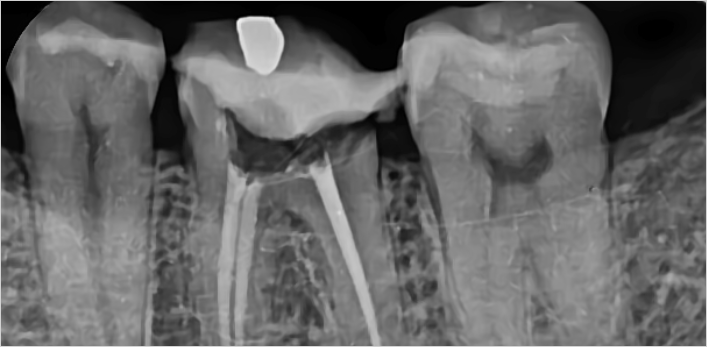

김** 환자분 (신경치료 진행 후 지르크라운으로 치료)

왼쪽아래 어금니 통증으로 방문,

보철물 제거 후 확인해보니 남은 치질이 별로 없어 post 추가 및 신경치료 진행 후 지르크라운으로 치료